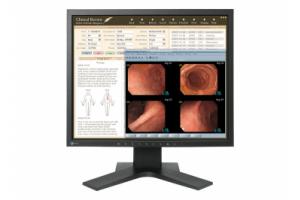

- Медицинские мониторы

Монохромный рентгенодиагностический ЖК-монитор с разрешением 3 мегапикселя.

Диагностический монитор LMD-DM30 предоставляет врачам четкое, яркое изображение с высокой степенью детализации. Монитор можно использовать в системах рентгенографии и других медицинских решениях, включая системы МРТ, КТ, системы компьютерной рентгенографии, прямой цифровой рентгенографии и цифровой маммографии.

Этот медицинский монитор отображает равномерное и стабильное изображение с высоким разрешением, а также обладает превосходной яркостью и контрастностью.